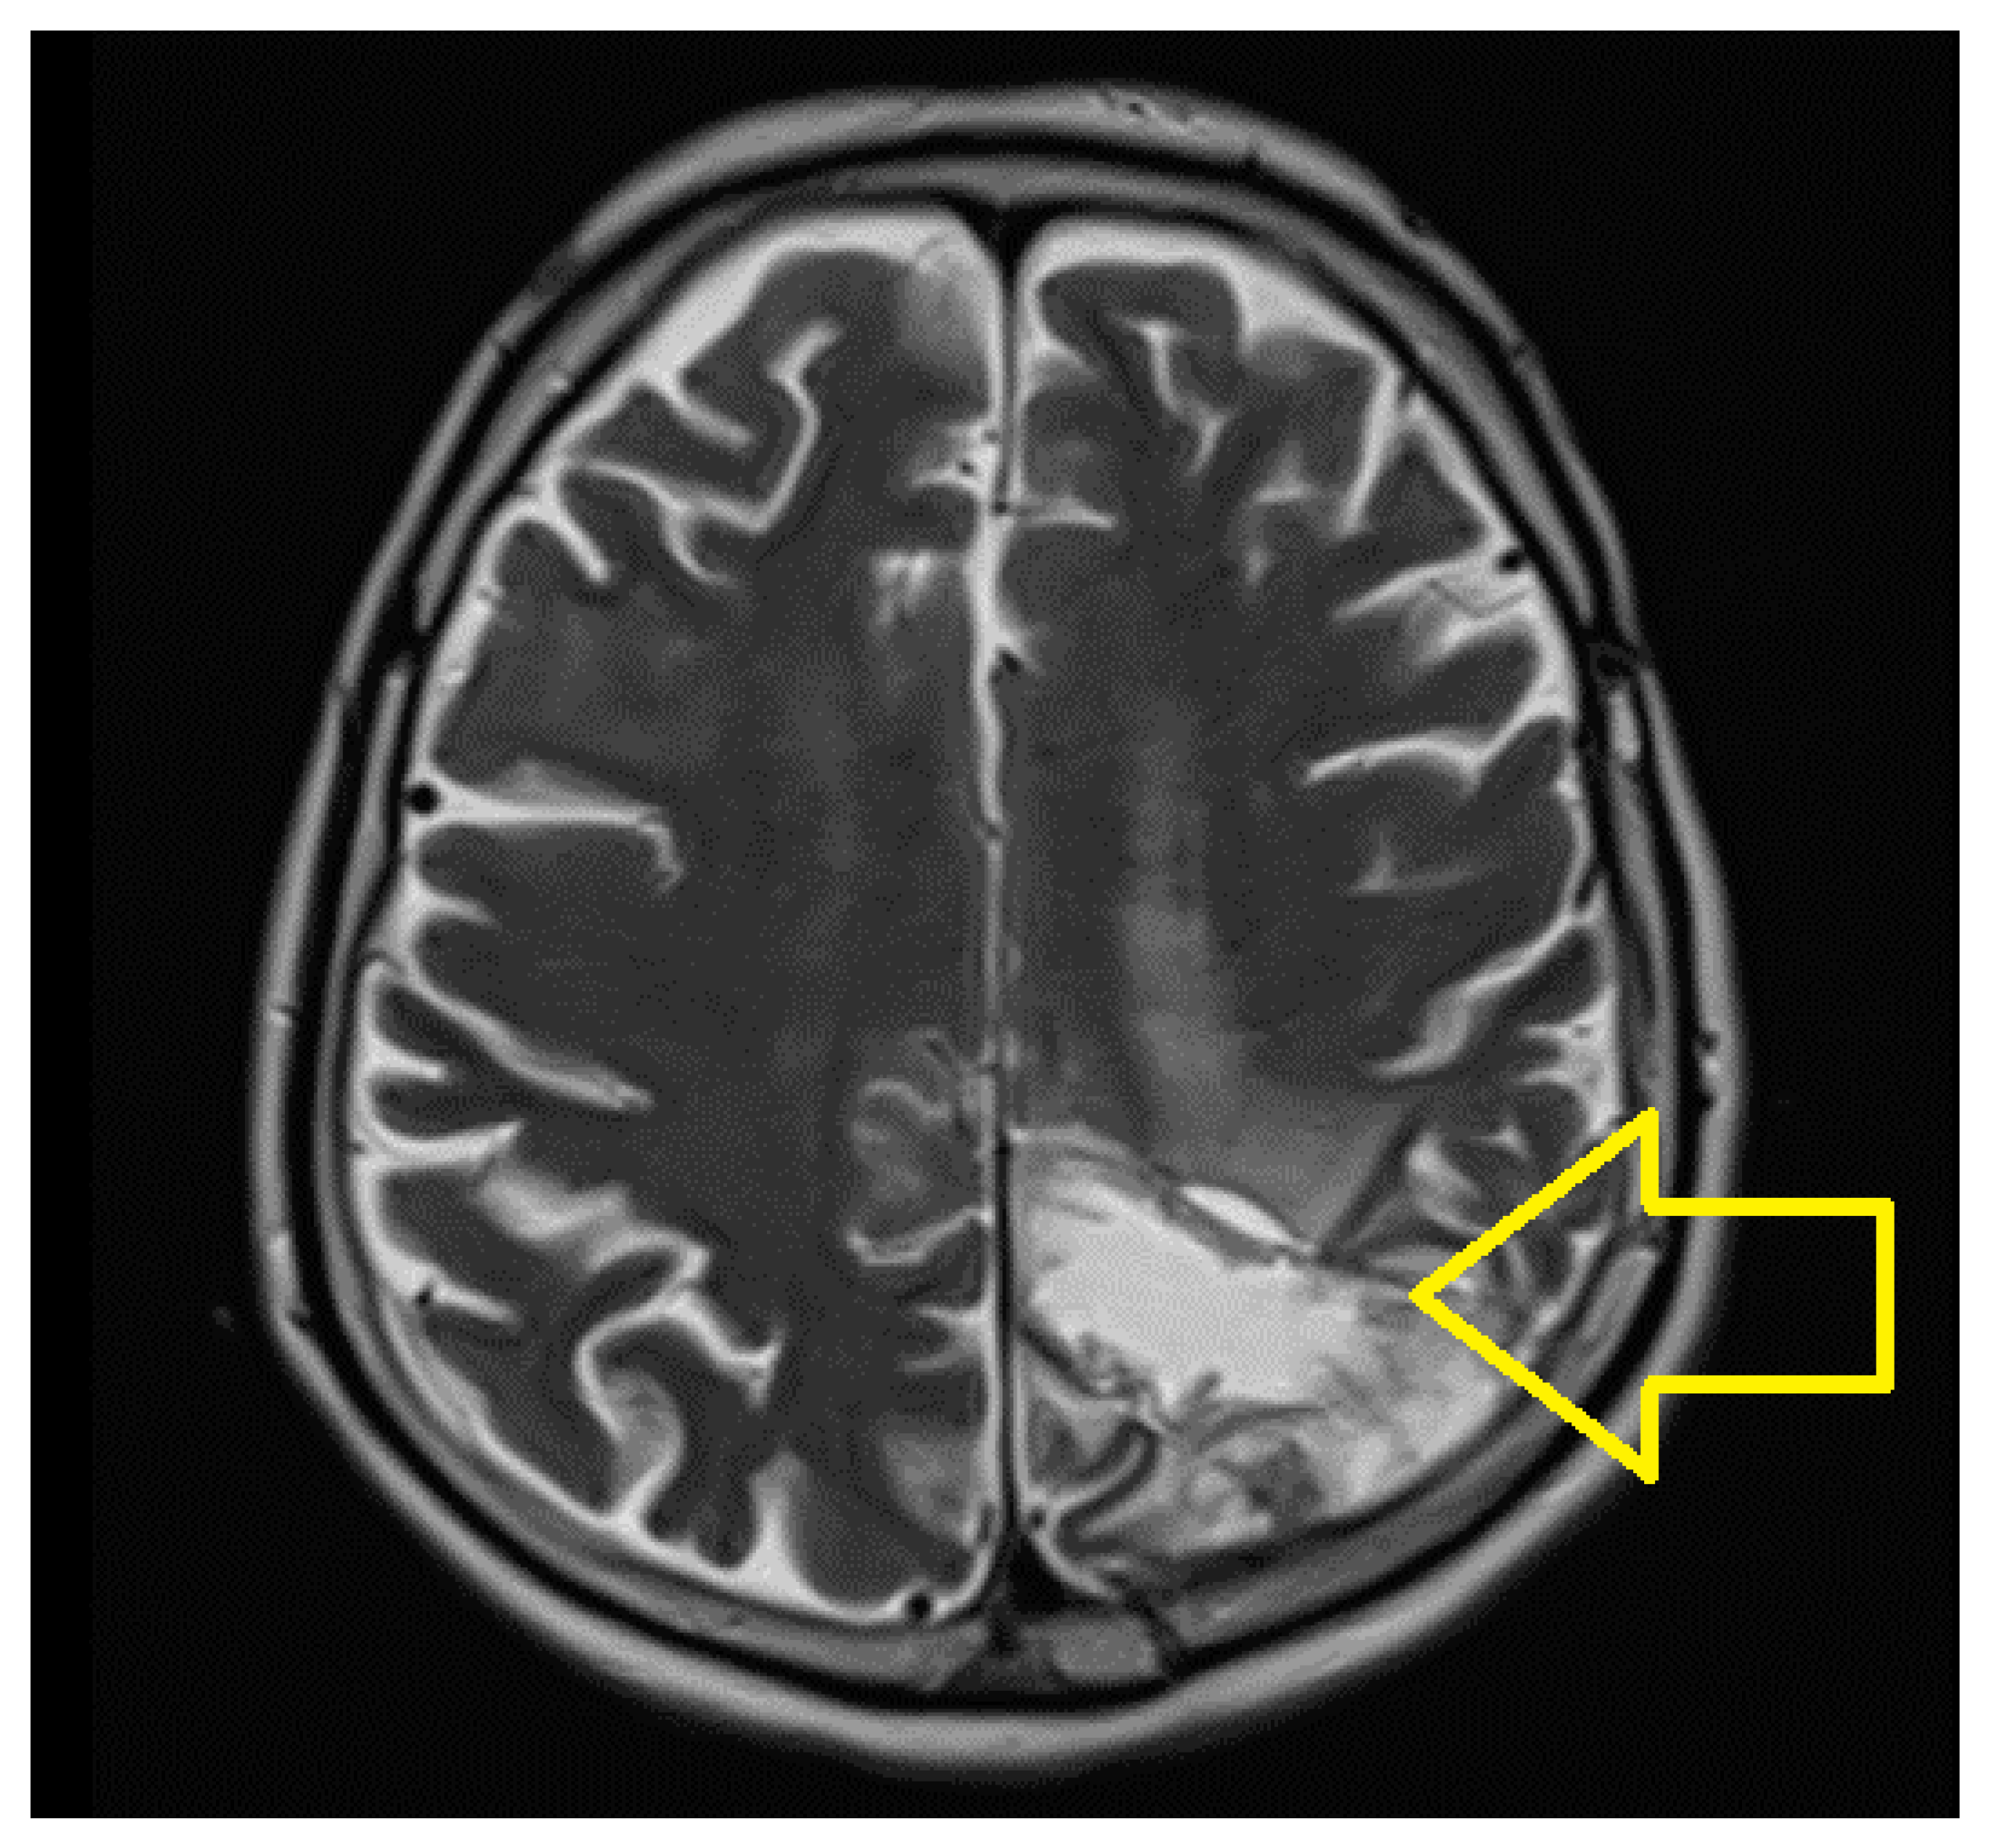

2. Case Report